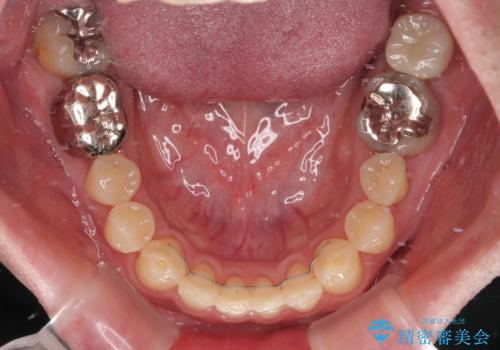

- 上下前歯の反対咬合と左下奥歯の痛みを気にして来院された患者様です。

歯並びや口元の印象、奥歯の咬み合わせから、非抜歯にて矯正治療を行うこととしました。

また、左下の奥歯は親知らずの影響で手前の歯の歯根までむし歯になってしまったため、親知らずとともに抜歯をし、インプラントによる補綴治療を行うこととしました。

インプラント埋入による仮歯の装着や、前歯の反対咬合の改善は比較的スムーズに達成されましたが、舌突出癖などの影響による、歯列全体のスペースを閉じることが難航し、期間がかかってしまいました。